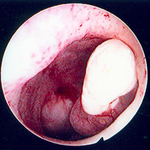

Hysteroscopic image of a large pedunculated submucous uterine fibroid

From the personal collection of Dr M.F. Mitwally and Dr R.J. Fischer; used with permission